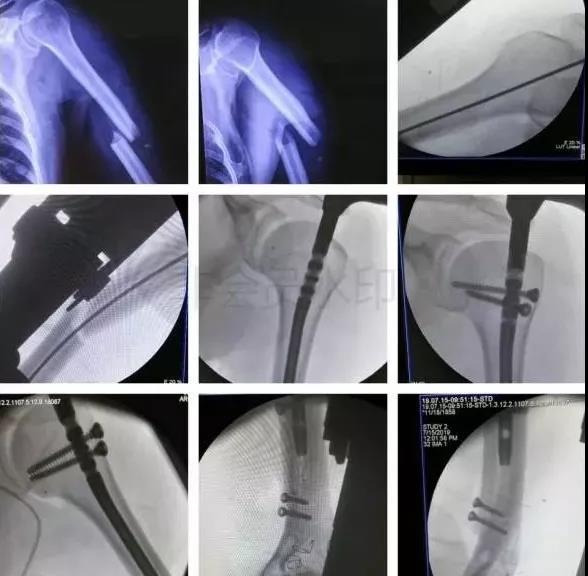

1)肱骨近端骨折

脱位伤及腋神经、血管等,或者由于肱二头肌长头腱卡压无法复位,立即手术。